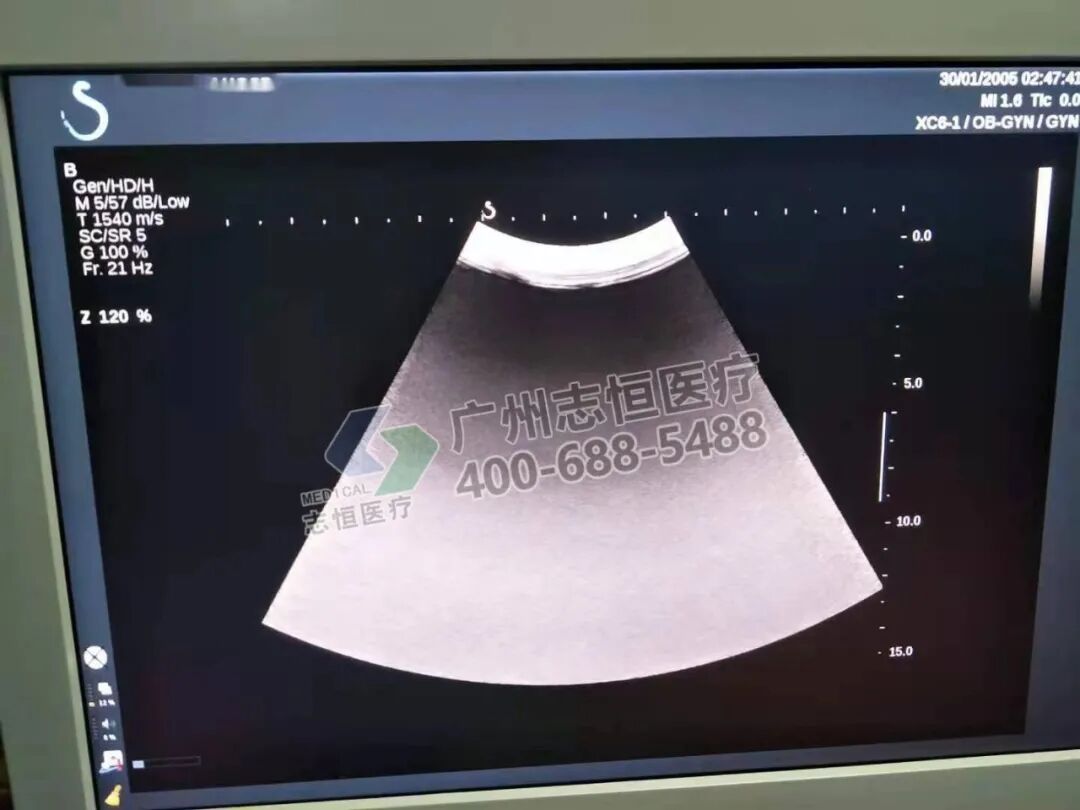

声科 Aixplorer 机器开机正常进入超声界面,腹部探头图像存在多个亮道伪影。

超声探头图像存在亮道伪影,可能为机器发射接收部分或探头本身故障导致。切换至浅表探头,探头图像同样存在亮道,排除探头本身故障可能,锁定为机器发射接收部分即DAB通道板故障。